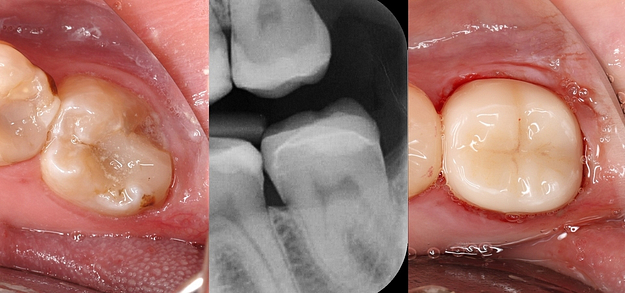

Digital technologies allow for extremely precise measurements and fabrication of dental restorations. This precision leads to a better fit, which can improve the longevity of the restoration and the overall health of the surrounding teeth and gums.

Digital restorations can often be designed, fabricated, and placed in a single visit, which is a significant improvement over traditional methods that may require multiple appointments.

With advanced software, dentists can create restorations that closely match the color, shape, and size of a patient’s natural teeth. This results in a more natural and aesthetically pleasing appearance.

Digital impression systems eliminate the mess, discomfort, and inaccuracies of traditional putty impressions, allowing for precise digital models.

CAD/CAM same-day crowns cut out the need for multiple appointments and temporary restorations.